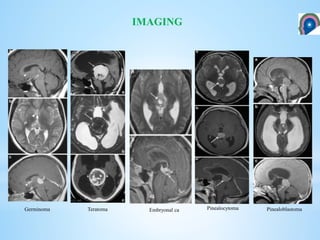

Germinoma Teratoma Embryonal ca Pinealocytoma Pinealoblastoma

IMAGING Germinoma Teratoma Embryonalca Pinealocytoma Pinealoblastoma